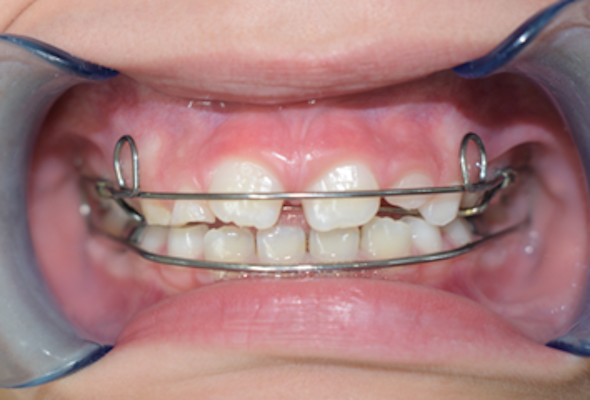

Caso de apiñamiento y sobremordida

Paciente pediátrico, masculino de 9 años de edad, acude acompañado de sus padres debido a la mala alineación de los dientes, y encías inflamadas (gingivitis). Buscan mejorar tanto la estética como la salud bucal desde una etapa temprana.

Se indicó un enfoque de ortodoncia interceptiva: aparatos para crear espacio en la arcaa, guía de erupción de dientes permanentes, corrección temprana de la mordida, y programa de higiene para controlar la gingivitis.

El paciente en su consulta de diagnóstico

Durante la valoración clínica se identificaron los siguientes hallazgos:

- Apiñamiento dental moderado en ambas arcadas

- Falta espacio para la erupción correcta de caninos superiores

- Sobremordida aumentada

- Encías inflamadas con enrojecimiento generalizado (gingivitis)

- Dentición mixta (presencia de dientes temporales y permanentes)